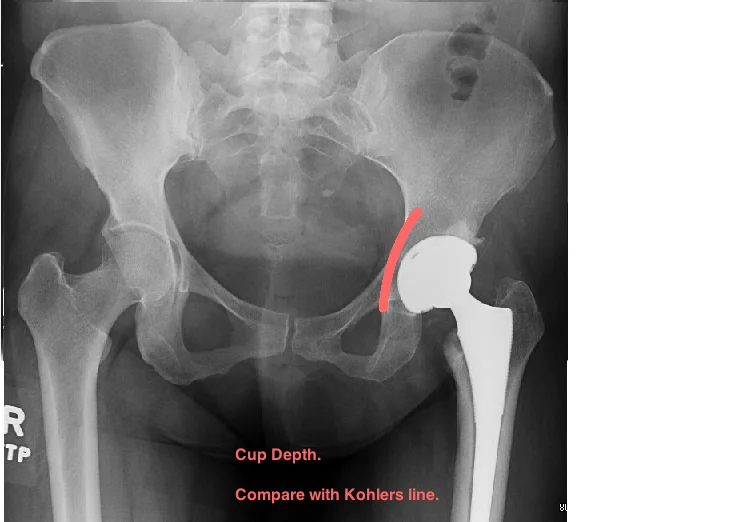

POST-OP EVALUATION

START BY EVALUATING CUP PLACEMENT